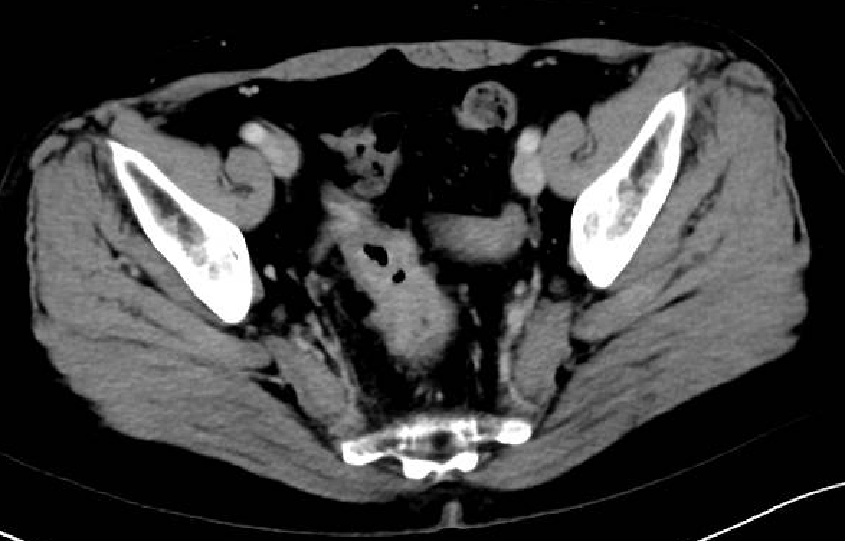

一 专家访谈 专家简介 于国华 教授 潍坊市人民医院 潍坊市肿瘤防治中心主任、潍坊市人民肿瘤医院院长、GCP机构副主任 潍坊市科技智库首席专家,省级重点学科负责人 中国临床肿瘤学会(CSCO)理事 山东省抗癌协会常务理事 潍坊市抗癌协会理事长 中国老年学学会舒缓治疗分会常务委员 中国老年学学会老年肿瘤专业委员会 中国老年学学会老年肿瘤专业委员会(CGOS)分子靶向分委会、肺癌分委会常务委员 山东省医学会肿瘤微创治疗分会副主任委员 山东省医学会姑息医学分会副主任委员 山东省肿瘤微创质量控制中心副主任委员 山东省医师协会肿瘤化疗医师分会副主任委员 山东省抗癌协会肿瘤化疗分会、肺癌分会、靶向治疗分会、心理治疗分会副主任委员 潍坊市医学会肿瘤化疗分会主任委员 潍坊市中西医结合学会肿瘤专业委员会主任委员 潍坊市肿瘤化疗专业质量控制中心主任 Q1 随着检查手段不断丰富,晚期结直肠癌的全程管理成为必然趋势。请您谈一谈我国在结直肠癌全程管理方面取得了哪些成果,未来应该朝着哪些方向努力? 我国在结直肠癌全程管理方面的进步成果,大概可以分为三个方面。 第一方面,随着医疗检测技术和诊疗理念的革新,我国早筛早治取得了良好进展。60~80年代我国检查技术相对落后,主要为粪便潜血试验展开有关肠道检查,而随着内镜技术的发展,肠镜检查逐渐普及,提高了结直肠癌早期患者的诊断率,推进了我国早诊早治的策略,使更多患者及早发现疾病并接受治疗。 第二方面,我国医疗制度具有优越性。随着我国全民医保的全面落实,“全民健康”理念的普及,就诊路径日益优化,更加快速便捷,使患者尽早获得诊断和治疗。 第三方面,国家癌症中心以及有关学协会的成立,推动了我国整体诊疗水平的不断提高。不仅为基层和各级医院搭建了良好的学习平台,推动了临床医生的再学习、再教育,也使得规范化诊疗、多学科协作(MDT)等优秀诊疗理念得以推广和实践。 第四方面,在内外科领域,药物治疗和手术治疗也是发展比较迅速。我国加速推进新药研发和医药服务创新,使更多药物尽快落地,惠及我国患者。相有关学协会积极组织形成了具有实践和指导意义的全程管理专家共识/指南,包括患者自身情况的评估、围手术期管理、治疗药物的选择、各线药物治疗方案、药物不良反应管理等。 关于结直肠癌全程管理未来的发展,需要以预防、规范化治疗和新药研发为抓手。 第一方面,预防是结直肠癌管理的第一步,未来有待在国家层面开展大规模的宣传教育,科普健康生活方式,令群众了解结直肠癌危险因素,从源头降低结直肠癌的患病风险。 第二方面,早筛早诊尽管已经取得显著成效,等仍需要深入基层,覆盖偏远贫困地区,使更多结直肠癌患者能够在早期发现,尽早干预,提升结直肠癌患者整体生存和预后。 第三方面,结直肠癌诊疗规范有待进一步提升,尤其需要在基层医疗单位加强规范化诊疗的理念。 第四方面,精准医学时代背景下,我们希望未来随着分子水平研究和精准医学研究的进展,在疗效监测和复发监测方面能使用更精准、更有价值的分子标志物动态监测。在手术前判断患者是否需要先做辅助化疗,在手术后判断是否需要进行复发监测,通过分子标志物可以更早地提示未来是否会复发,是否需要提前干预,如果复发,分子标志物可以再次作为监测指标指导治疗。 第五方面,我们还需加大研发力度,开发更多新机制、新靶点的药物,进一步提升晚期结直肠癌的疗效。 Q2 长期以来,化疗始终是肿瘤治疗领域的基石。其中,曲氟尿苷替匹嘧啶片(TAS-102)作为新型口服化疗药,问世以来不断为结直肠癌领域打开新的治疗格局,请您谈谈该药在中国的上市是基于怎样的研究成果? TAS-102在中国的获批是基于国际多中心 RECOURSE 研究和亚太TERRA研究的结果。RECOURSE研究是TAS-102的国际多中心Ⅲ期临床研究,显示TAS-102较安慰剂显著延长中位OS时间(7.1个月对比5.3个月)和中位PFS时间(2.0个月对比1.7个月),死亡风险和疾病进展风险分别降低32%和52%。此后,有众多中国临床专家参与的TERRA研究,证实了TAS-102在亚洲人群的安全性和有效性,TERRA研究重复出了RECOURCE研究的结果,TAS-102组患者的中位OS时间(7.8个月对比7.1个月)和PFS时间(2.0个月对比1.8个月)得到显著改善,死亡风险和疾病进展风险分别降低21%和57%。这两项关键研究成功改写了包括ESMO、NCCN、CSCO等中外权威指南的推荐。 而且,这两项研究中,TAS-102的不良反应均以血液学毒性为主,有症状的不良反应发生率低。鉴于其良好的安全性和耐受性,TAS-102与其他药物联合用于肠癌也在研究中进行了探索并取得了不错的结果。 Q3 晚期结直肠癌的发生通常预示着预后相对较差、患者生存期不长,但依然有治愈的可能,这关系到临床治疗用药方案的决策。今年上半年发布的CACA-RC指南推荐不适合强烈治疗患者应用TAS-102联合贝伐珠单抗,作为晚期不可切除结直肠癌姑息一线治疗方案。请您谈谈该推荐治疗对我国晚期不可切除结直肠癌的临床治疗产生了怎样的影响? 晚期转移性结直肠癌的标准化疗方案在指南中是以奥沙利铂或伊立替康为基础的FOLFOX和FOLFIRI方案,在此基础上,可以联合西妥昔单抗或贝伐珠单抗,但是,依旧有部分患者身体状况无法耐受加强化疗,少数患者因为高敏可能出现药物过敏,针对这一类患者,治疗方案的选择非常有限且预后情况并不理想。临床上往往推荐口服化疗药物+贝伐珠单抗方案。 2022年CACA-RC指南基于TASCO1研究的结果,推荐拒绝静脉化疗或不能耐受强烈治疗、易敏的晚期肠癌患者姑息一线选择TAS-102+贝伐珠单抗方案。TASCO1研究是一项旨在随机比较TAS-102+贝伐珠单抗和卡培他滨+贝伐珠单抗在一线治疗不可接受强烈治疗的不可切除转移性结直肠癌的Ⅱ期研究。研究结果显示:TAS-102组延长患者mPFS时间1.41个月(9.23个月对比7.82个月);延长患者mOS时间4.64个月(22.31个月对比17.67个月)。安全性分析也提示TAS-102+贝伐珠单抗治疗具有良好的耐受性,它最常发生的3/4级不良事件是中性粒细胞减少症。严重的发热性中性粒细胞减少症发生率约为4%。TAS-102+贝伐珠单抗方案因其高效、低毒的特点为不适合强烈治疗的转移性结直肠癌患者及老年患者带来了新的希望,其疗效与生存获益令人期待。 Q4 近年来,结直肠癌领域联合治疗的研究探索不断取得进步。请您谈谈,还有哪些研究进展为TAS-102联合贝伐珠单抗奠定一线治疗地位打下基础? 近年来,多项临床研究不断为TAS-102的临床可及性打下良好基础,DANISH研究将TAS-102与贝伐珠单抗联合用于转移性结直肠癌二线及以上治疗,发现联合组较TAS-102单药组疗效更好,中位PFS时间(4.6个月对比2.6个月)和OS时间(9.4个月对比6.7个月)显著延长,且联合组安全性可控,未出现非预期的不良反应。日本C-TASK-FORCE研究和欧洲DANISH研究均显示,对于PS为0~1分的转移性结直肠癌患者,TAS-102+贝伐珠单抗三线治疗实现了超过4.5个月的中位无进展生存期(PFS),超越了既往单药三线治疗的总体水平,且未显著增加不良事件(AEs)。TAS-102+贝伐珠单抗4周方案治疗转移性结直肠癌显示了良好的抗肿瘤活性。日本BiTS研究确证了双周方案可在不影响疗效的前提下,明显降低中性粒细胞减少症发生率。日本KSCC 1602研究和欧洲TASCO1研究都成功探索了FTD/TPI+贝伐珠单抗用于转移性结直肠癌一线治疗的疗效和安全性。 二 病例分享 专家简介 任海朋 主任 潍坊市人民医院 潍坊市人民医院肿瘤内科副主任,副主任医师 中国抗癌协会肿瘤微创治疗专业委员会委员 中国抗癌协会肿瘤消融治疗专业委员会委员 山东省健康管理协会消化道肿瘤防治分会副主任委员 山东省抗癌协会青年理事会常务理事 山东省医学会肝脏肿瘤多学科联合委员会委员 山东省抗癌协会消化道肿瘤分会委员 潍坊市医学会结直肠癌多学科联合专委会副主任委员 潍坊市医学会肿瘤微创治疗专业委员会副主任委员 潍坊市医师协会肿瘤化疗医师分会副主任委员 肖海凤 医师 潍坊市人民医院 潍坊市人民医院肿瘤内科主治医师,硕士 山东省抗癌协会化疗分会青年委员会委员 山东省疼痛医学会癌痛与姑息治疗专业委员会委员 山东省医学会科学普及分会肿瘤科普学组委员 山东省医学会精准医学分会消化道肿瘤学组委员 潍坊市医学会化疗专业委员会委员兼秘书 潍坊市抗癌协会乳腺癌专业委员会委员 潍坊市抗癌协会妇科肿瘤分会委员 潍坊市医学会第三届肛肠外科专业委员会青年学组委员 01 基本情况 基本情况:史xx,女,57岁,既往体健,无特殊病史,无家族史。 简要病史: 2020.1 患者出现大便带血,为暗红色,与大便相混,伴大便次数增多3~4次/天,大便不成形,伴肛门坠胀及里急后重感。 2020.4 就诊于潍坊市人民医院消化内科门诊,行肠镜示距肛门10cm环周隆起性病变,肠腔狭窄,镜身不能通过,考虑直肠癌,活检病理示腺癌(中分化)。 2020.4.16 就诊于我院肛肠外科一区,行胸腹盆部CT提示乙状结肠占位,考虑肿瘤,盆腔肿大淋巴结,双肺多发转移瘤。 诊断:直肠癌(cT3N+M1a,IVa期)。 2020.4.18 肺多发转移(CT) 2020.4.18 直肠原发灶(CT) 2020.5.12 基因检测 KRAS:Exon2、Exon3无突变;NRAS:Exon2、Exon3 无突变;BRAF:Exon15(V600E)无突变。UGT1A1*28:TA6/7,UGT1A1*6:G/G。MSS。 02 治疗经过 因直肠原发灶进镜困难,肠腔狭窄,发生肠梗阻风险较大,建议先行原发灶切除,后行全身抗肿瘤治疗。 2020.4.23 行直肠癌根治术(前切除术)+回肠预防性造口术+肠粘连松解术。 术后病理 一线治疗经过 2020.5.18至2021.1.31 行奥沙利铂甘露醇注射液225mg d1+卡培他滨1.5g bid d1-14方案化疗8周期。 不良反应:胃肠道反应不著,骨髓抑制最重2度。 疗效评价:5周期后疗效评价为PR,8周期后疗效评价为PD。 双肺转移灶(一线) 二线治疗经过 入住我科,ECOG 0分,身高159cm,体重65kg,体表面积1.64m2。 2021.3.9、2021.3.29、2021.4.12、2021.5.6、2021.5.25、2021.6.21、2021.7.9、2021.7.28、2021.8.15行西妥昔单抗800mg d1+伊立替康300mg d2+氟尿嘧啶650mg iv,4000mg civ 46h+左亚叶酸钙325mg d2化疗9周期。 不良反应:胃肠道反应不著,骨髓抑制2度。 疗效评价:缩小的SD。 双肺转移灶(二线) 三线治疗经过 2021.9至2022.5.6 口服呋喹替尼5mg qd d1-21 q28d治疗。 不良反应:高血压病1级,轻度肝功损伤。 疗效评价:2个月后疗效评价PR,7个月后肺内病灶增大,肝内出现新发病灶,疗效评价PD。 双肺转移灶(三线) 肝脏(新发病灶) 四线治疗经过 2022.5至今 开始应用贝伐珠单抗300mg d1联合TAS-102 55mg bid d1-5双周治疗。 不良反应:高血压2级,继发性甲状腺功能减退,白细胞减少I度,中性粒细胞减少2度,贫血1级。 疗效评价:PR。 03 病例小结 04 心得体会 TAS-102是一种新型口服细胞毒药物,是口服的氟尿嘧啶类药物,作用机制不同于氟尿嘧啶,可用于氟尿嘧啶耐药患者。 国际RECORSE和亚太TERRA研究证实,TAS-102在mCRC治疗中具有一致的疗效和安全性:1.显著延长mCRC患者生存期,降低死亡和疾病进展风险,尤其对于≥65岁患者获益更显著;2.显著延缓体能下降,为持续治疗提供体能储备;3.主要不良事件为血液学毒性。 双周TAS-102联合贝伐单抗不仅不降低疗效,而且明显降低中性粒细胞减少症发生率。 *本文仅代表专家观点,并经专家审校。